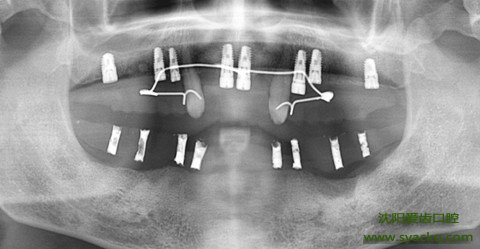

早孕是将人工材料制成的形似牙根的种植体经手术植入到人体的颌骨内或骨膜下,愈合后支持假牙的一种方法。种植义齿通常是有两部分组成的,一部分是我们肉眼看不见的位于颌骨内的种植体;另一部分是我们看得到的与种植体相连穿出并暴露出牙龈的假牙部分。我们常见的早孕是由一种叫钛的金属制造的,它有良好的稳定性和生物相容性,也无毒无副作用,无磁性,无刺激。据报道最早植入的患者的修复和种植体已有近40多年,依然行使正常功能。

早孕像天然牙的仿生性给我们带来更多的好处,比如感觉更舒服更美观,它没有活动假牙的妨碍发音引起异物感的基托和卡环;早孕将咬合力通过牙齿到种植体再传递到颌骨里,这样的仿生理的刺激就可以延缓牙槽骨的吸收,而传统的修复方法是由邻牙或黏膜作为支持,力量由假牙传达到基牙或黏膜再传到颌骨上的。